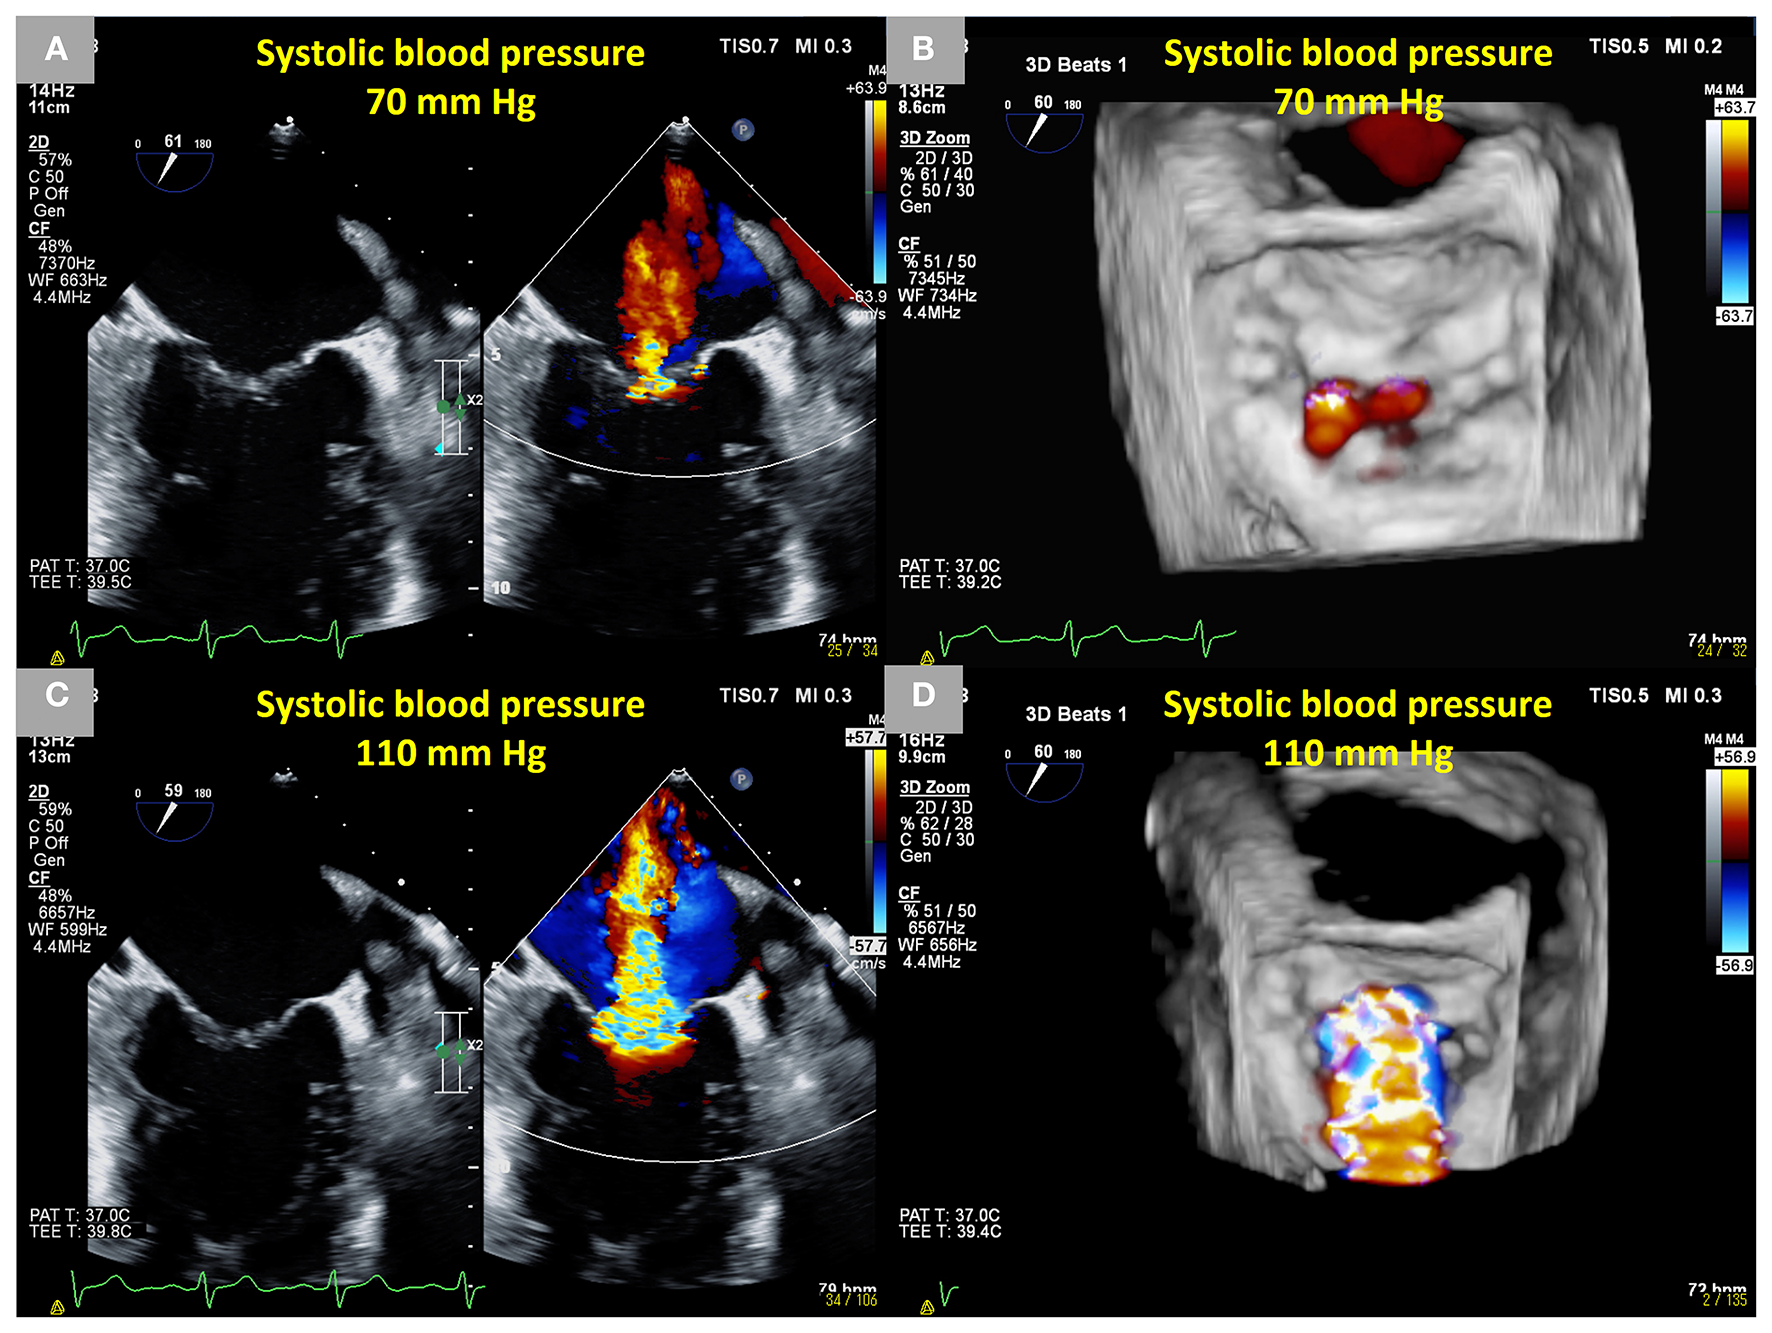

Figure 1

Dynamic changes in SMR during transesophageal echocardiography in a 66-year-old male patient who had an anterior old myocardial infarction and heart failure with reduced ejection fraction. Mild SMR (EROA 0.10 cm2) under sedation using midazolam under a systolic blood pressure of approximately 70 mm Hg. (A) Two-dimensional B-mode and color Doppler images from the intercommissural view and (B) a three-dimensional color Doppler image from the en-face view. Dynamic severe SMR (EROA 0.51 cm2) under an elevated systolic blood pressure of approximately 110 mm Hg using norepinephrine. (C) Two-dimensional B-mode and color Doppler images from the intercommissural view and (D) a three-dimensional color Doppler image from the en-face view. SMR, secondary mitral regurgitation; EROA, effective regurgitant orifice area.